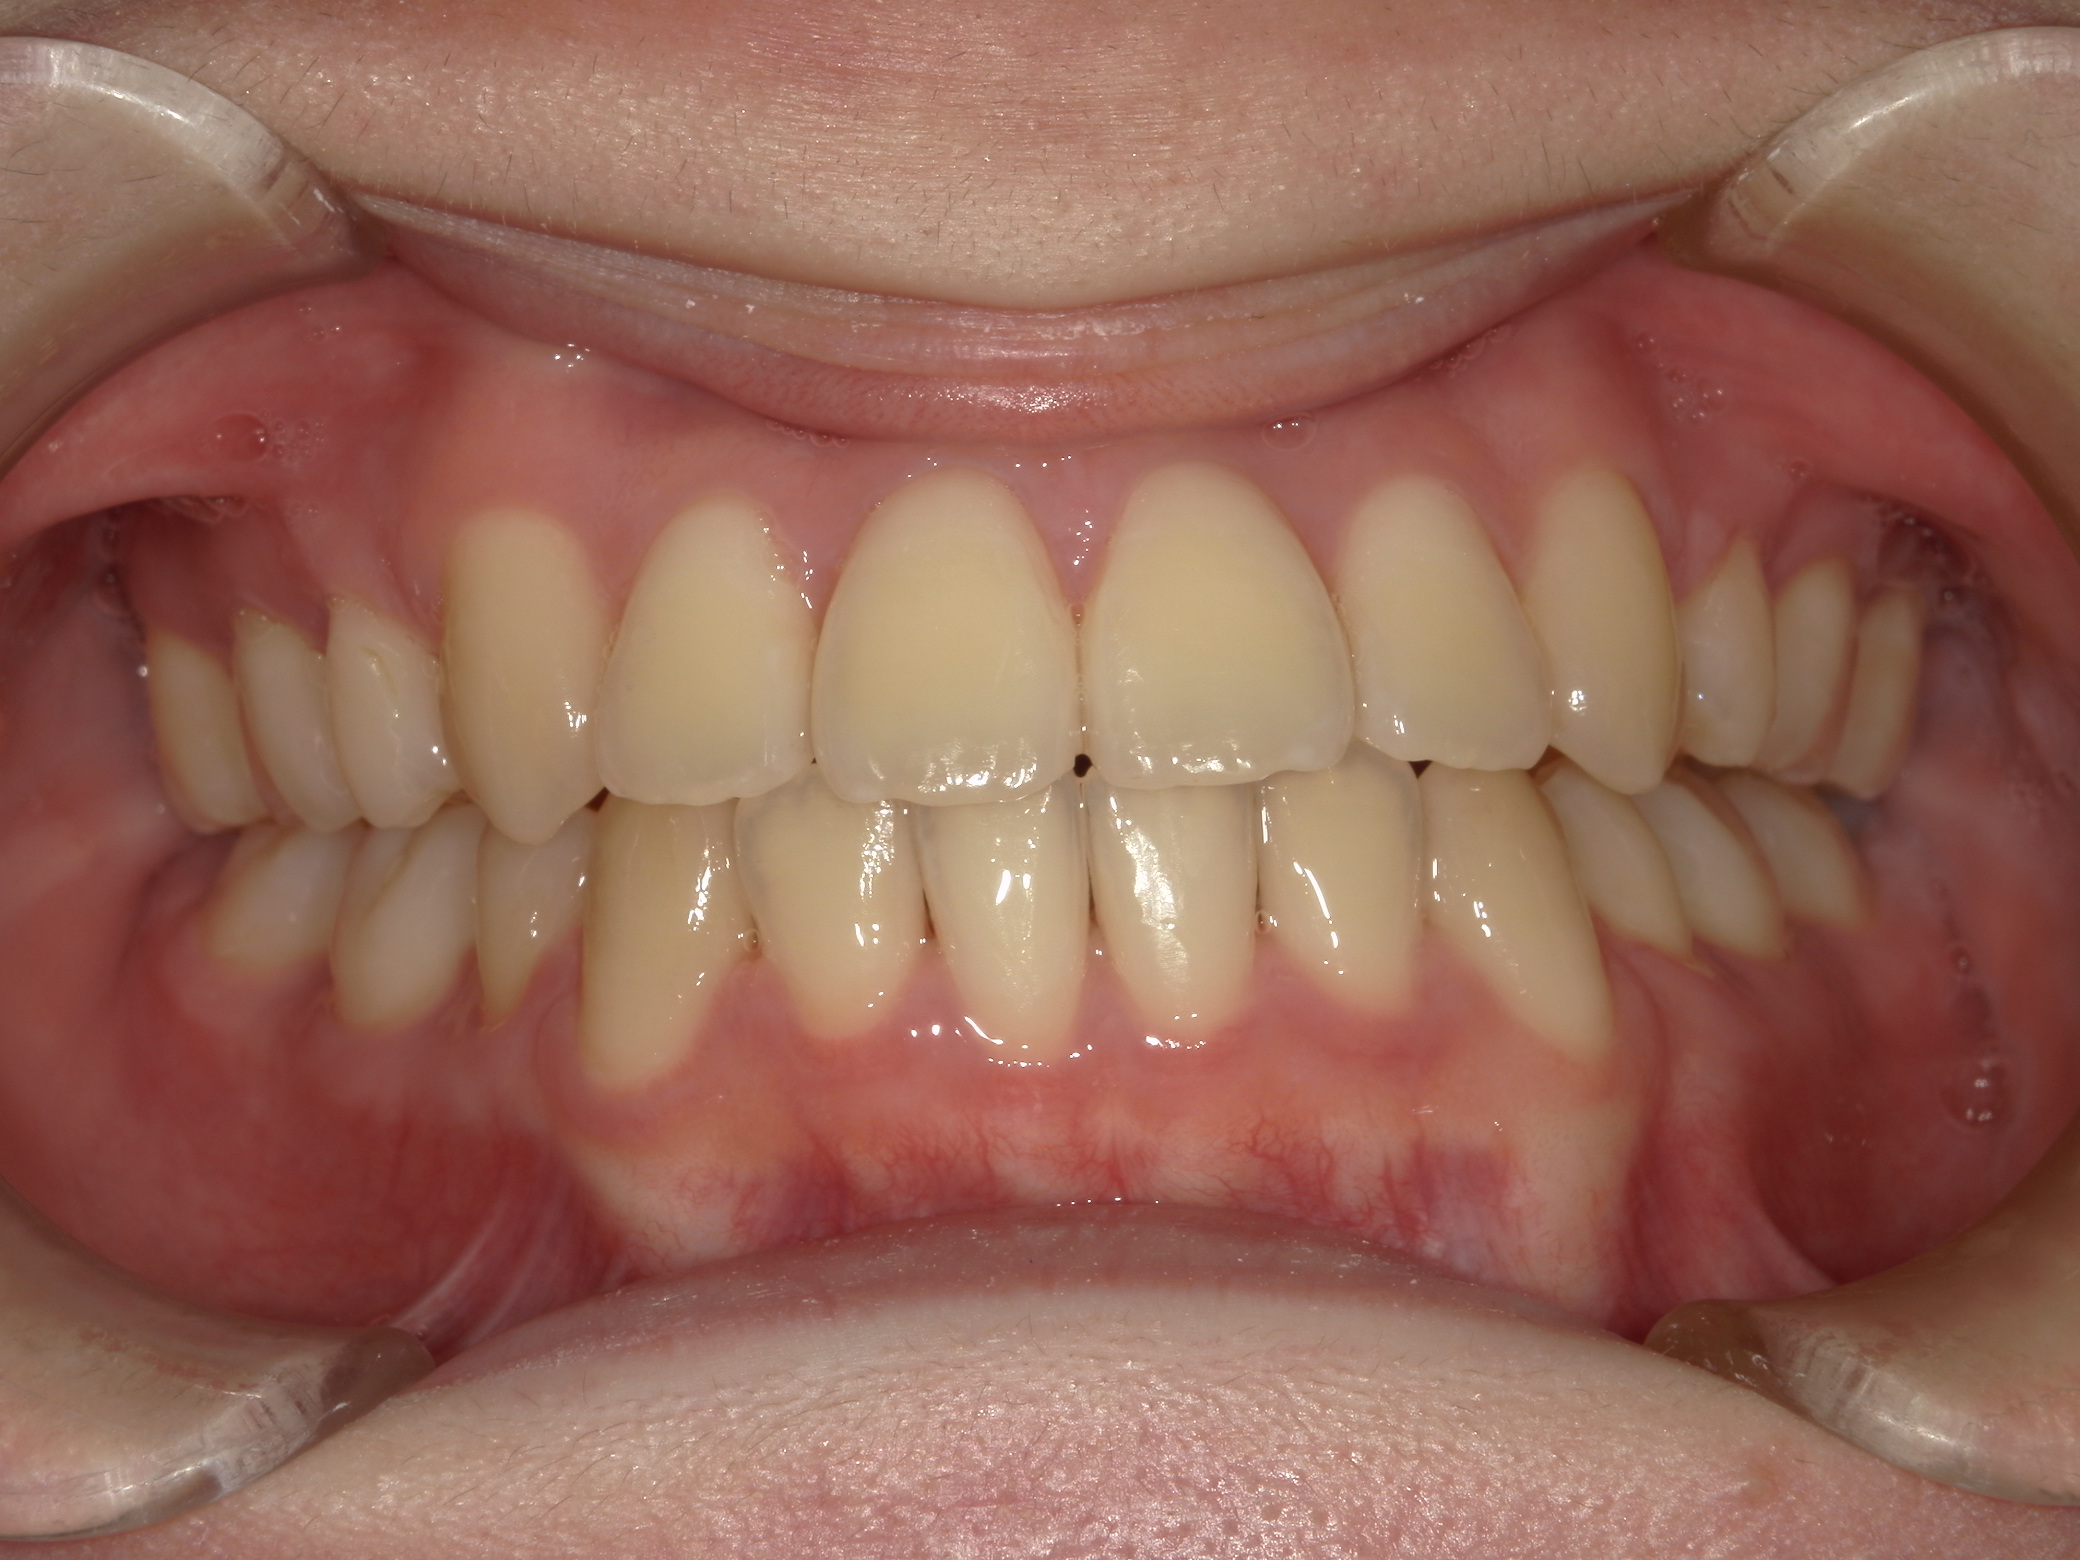

歯並び・かみ合わせ・口元の見た目が気になる

| 年齢・性別 | – |

|---|---|

| 主訴 | 歯並び・かみ合わせ・口元の見た目が気になるとの事でご相談があり矯正の治療を行いました。 |

| 治療期間・回数 | 2年 |

| 費用 | 1,001,000円 |